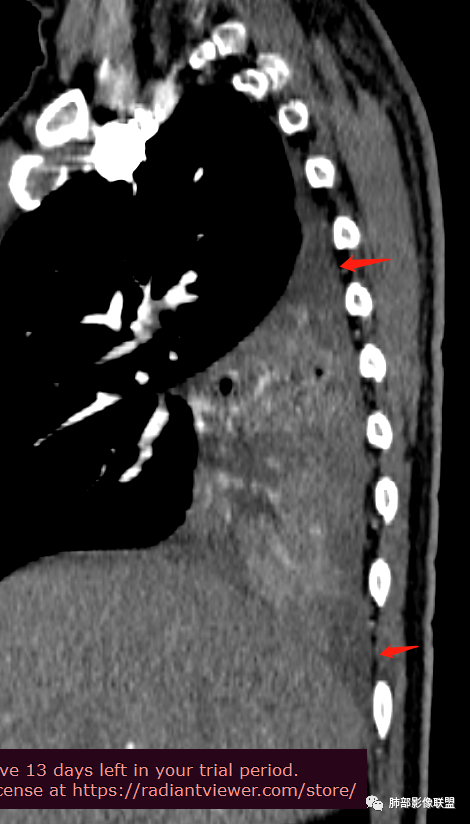

中心性起源:主要位于段及段以上支气管,多为气管、支气管腔内软组织结节及肿块,卵圆形或分叶状,沿支气管壁生长,最长径与支气管走行长径平行,与近心端支气管管腔呈钝角,支气管内可见“空气新月征”。

周围型MEC少见,且CT表现不具特征性,周围型结节或肿块,可出现分叶、毛刺等恶性征象,坏死、空洞较常见CT平扫多为欠均匀的低-中等密度,增强扫描后病灶以轻-中度不均匀强化为主。

肿块内钙化:MEC较其他类型肺癌钙化率高,约50%病例中可见斑点或颗粒状钙化。钙化可能与病程较长,局部血供少致营养不良性钙化有关,肿瘤支气管远端可出现阻塞性肺炎及肺不张征象。